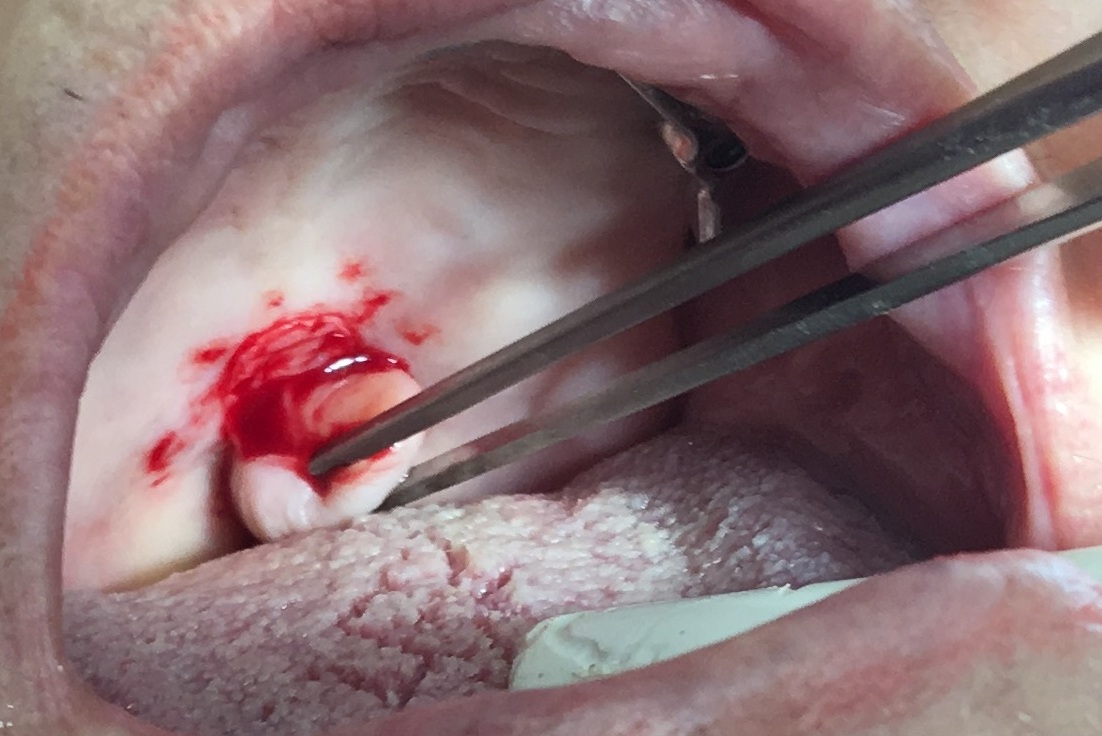

WebLa mayoría de las heridas leves, como pequeños cortes o raspones, pueden curarse por sí solas en unos pocos días. Sin embargo, las heridas más graves pueden tardar entre. WebEn un adulto los tiempos se prolongan considerablemente, pudiendo tardar hasta 3 años en colocarlo en su sitio, e incluso fracasar en el intento. Por supuesto, como ya te dicen, es. WebSegún expertos en odontología, cuando se extrae un diente, se genera tejido de granulación en pleno proceso de sanación de la inflamación. Éste, aparece dentro de una semana y protege la extracción hasta que se forme un hueso nuevo, lo cual puede tomar unas ocho semanas. En la cirugía de colgajo de las encías, un especialista ... WebEl tiempo de cicatrización es el período que tarda una herida en sanar. Y aunque el cuerpo humano ante una herida, comienza un proceso natural para controlar. WebPor lo general, el cirujano dental extraerá los puntos después de aproximadamente 1 semana. Algunas veces, la cirugía causa hematomas, hinchazón y dolor, que también requerirá tiempo para ... WebLa mayoría de las veces, la reparación del paladar hendido se hace cuando el niño es mayor, entre 9 meses y 1 año de edad. Esto permite que el paladar cambie a medida que el bebé crece. Realizar la reparación cuando el niño tiene esta edad ayudará a prevenir problemas posteriores en el lenguaje a medida que el niño se desarrolle. Web¿Cuánto tarda en cicatrizar una herida en el paladar? Sin embargo, en la farmacia es posible comprar medicamentos que te ayudarán a minimizar las molestias y acelerar el.

WebTiempos de cicatrización según área corporal perforada: - Cartílago de la oreja: de 6 a 7 meses. - Lóbulo de la oreja: de 4 a 6 semanas. - Ceja: de 6 a 8 semanas. - Fosas. Web¿Cuánto tiempo tarda en cicatrizar el paladar? Además de los puntos de sutura que al cabo de los días debe quitarte el dentista, también la escisión del paladar debe regenerarse.. WebSuele considerarse la etapa final de una enfermedad o lesión, y en algunos casos también supone el principio de un problema emocional en función de la localización, tamaño o forma de la cicatriz. La cicatrización es un proceso activo que se prolonga durante 12-18 meses. Podemos distinguir diferentes tipos: